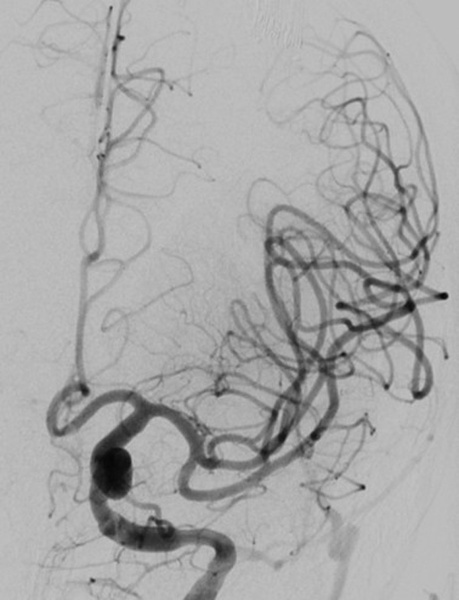

Results after first pass TICI 3

• Complete recanalization (mTICI 3) of the left carotid T occlusion was achieved after a single aspiration pass, with a puncture-to-recanalization time of 11 minutes